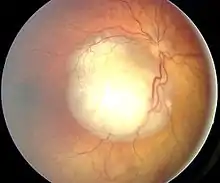

Fundoscopic examination

- Awake examination with attention to visual acuity, extraocular movement, pupillary examination, slit-lamp examination, and indirect ophthalmoscopy

- Ocular fundus examination under general anesthesia: white tumor with angiomatous dilation of the vessels

- Unilateral or bilateral nature of the lesions

- Number of tumors

- Location in the retina (posterior pole, anterior retina), and anatomica relations with optic disc and macula

- Tumor size (diameter, thickness)

- Subretinal fluid and tumor seeds

- Vitreous seeding (localized vs diffuse)